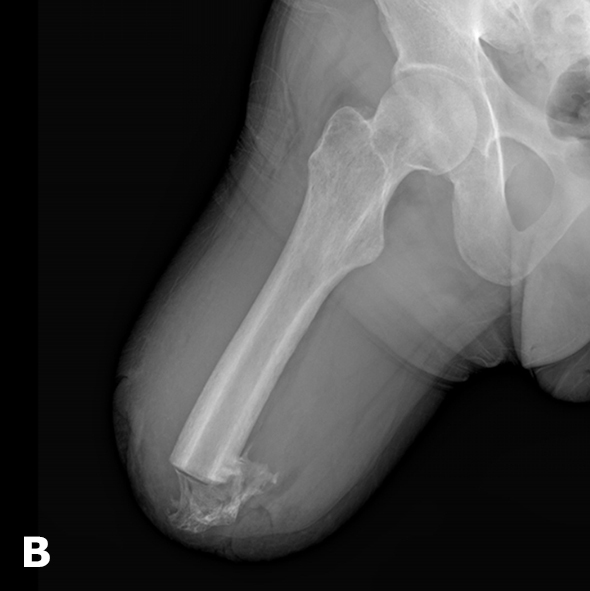

- 732 patients (704 men and 28 women; mean age 36.2 ± 10.2 years) with gunshot injuries to the peripheral nerves of the extremities requiring surgical repair (Fig. 2);

Fig.2. Principal types of gunshot injury to peripheral nerves: (a) nerve compression resulting from fibrotic degeneration of the mesoneurium;(b) formation of a fibrotic band (a zone of peripheral nerve fixation) preventing normal nerve gliding and leading to ischemia;(c) anatomical injury—complete nerve transection with a defect of the nerve tissue

- 56 patients (all men; mean age 30.9 ± 7.8 years) with post-amputation sequelae following gunshot trauma, who developed pain syndrome due to the formation of painful neuromas (Fig. 3).

Approximately 53.1% of gunshot-related peripheral nerve injuries were associated with a primary nerve defect and required autoneuroplasty.